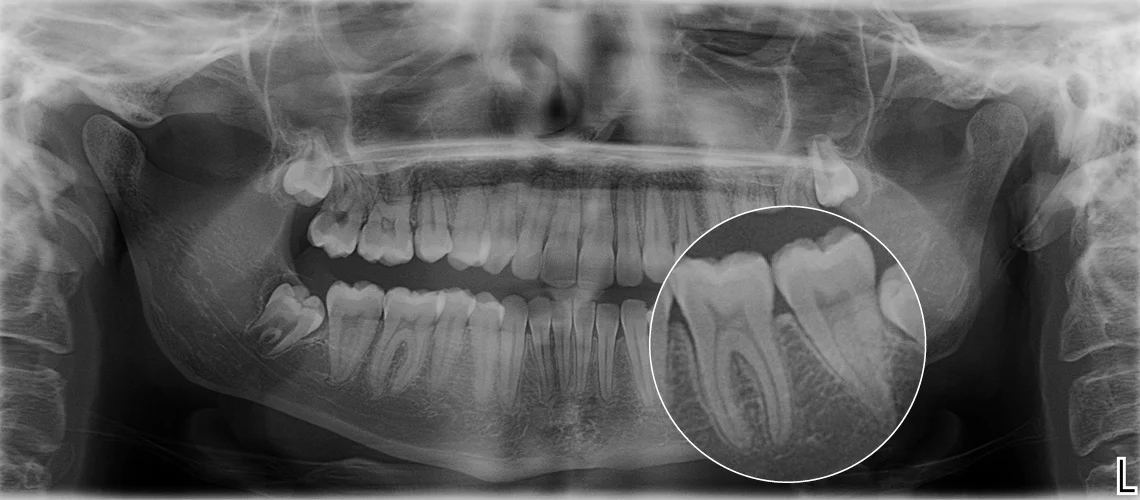

Панорамный снимок зубов (ортопантомограмма) — позволяет увидеть сразу все зубы и челюсти на одном изображении.

3D снимок зубов и челюсти (КТ) — даёт объёмное изображение в высоком разрешении, необходимое перед имплантацией или удалением зуба мудрости.

Все процедуры проводятся на аппарате Planmeca 3D, обеспечивающем высокую чёткость при минимальной дозе облучения.

Современное оборудование — точность изображения до 0,1 мм, низкое излучение.